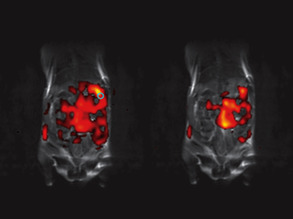

Magnetic Attractions

Nanobiotechnology Week